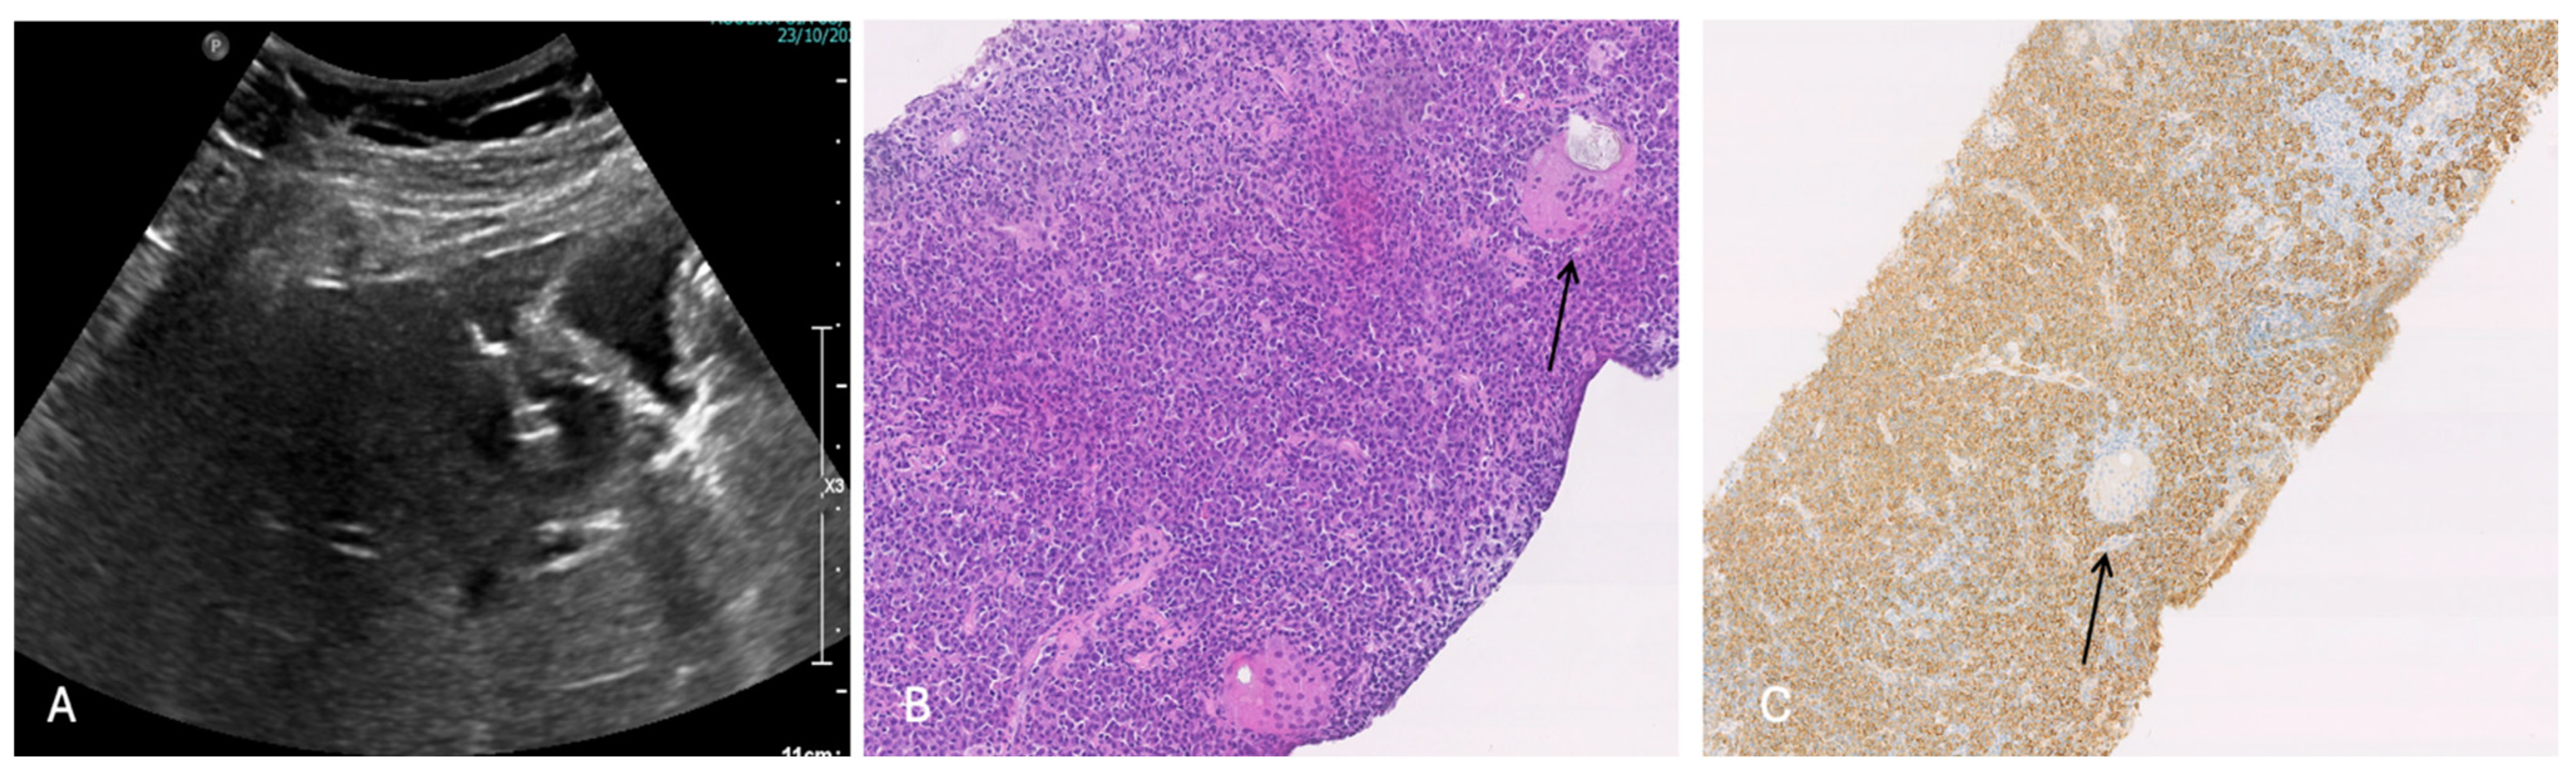

An ultrasound (US)-guided tumor biopsy revealed, at pathology with hematoxylin and eosin staining, inflammatory cells infiltration with giant cells and plasma cells (CD 138+, polyclonal kappa and lambda chains, no IgG4 expression). Finally, no tumor cells or any cytological atypia were revealed (Figure 6).

Figure 6.

(A) Ultrasound (US)-guided biopsy of S5 nodule next to gallbladder; (B) pathological examination of the tumor showed fibrosis accompanied by lymphoplasmacytic infiltration (hematoxylin and eosin staining, low power × 100 HE); (C) Immunohistochemical staining shows inflammatory cells infiltration with giant cells (black arrow) and plasma cells (CD 138+, polyclonal kappa and lambda chains, no IgG4 expression) (low power × 100 HE).